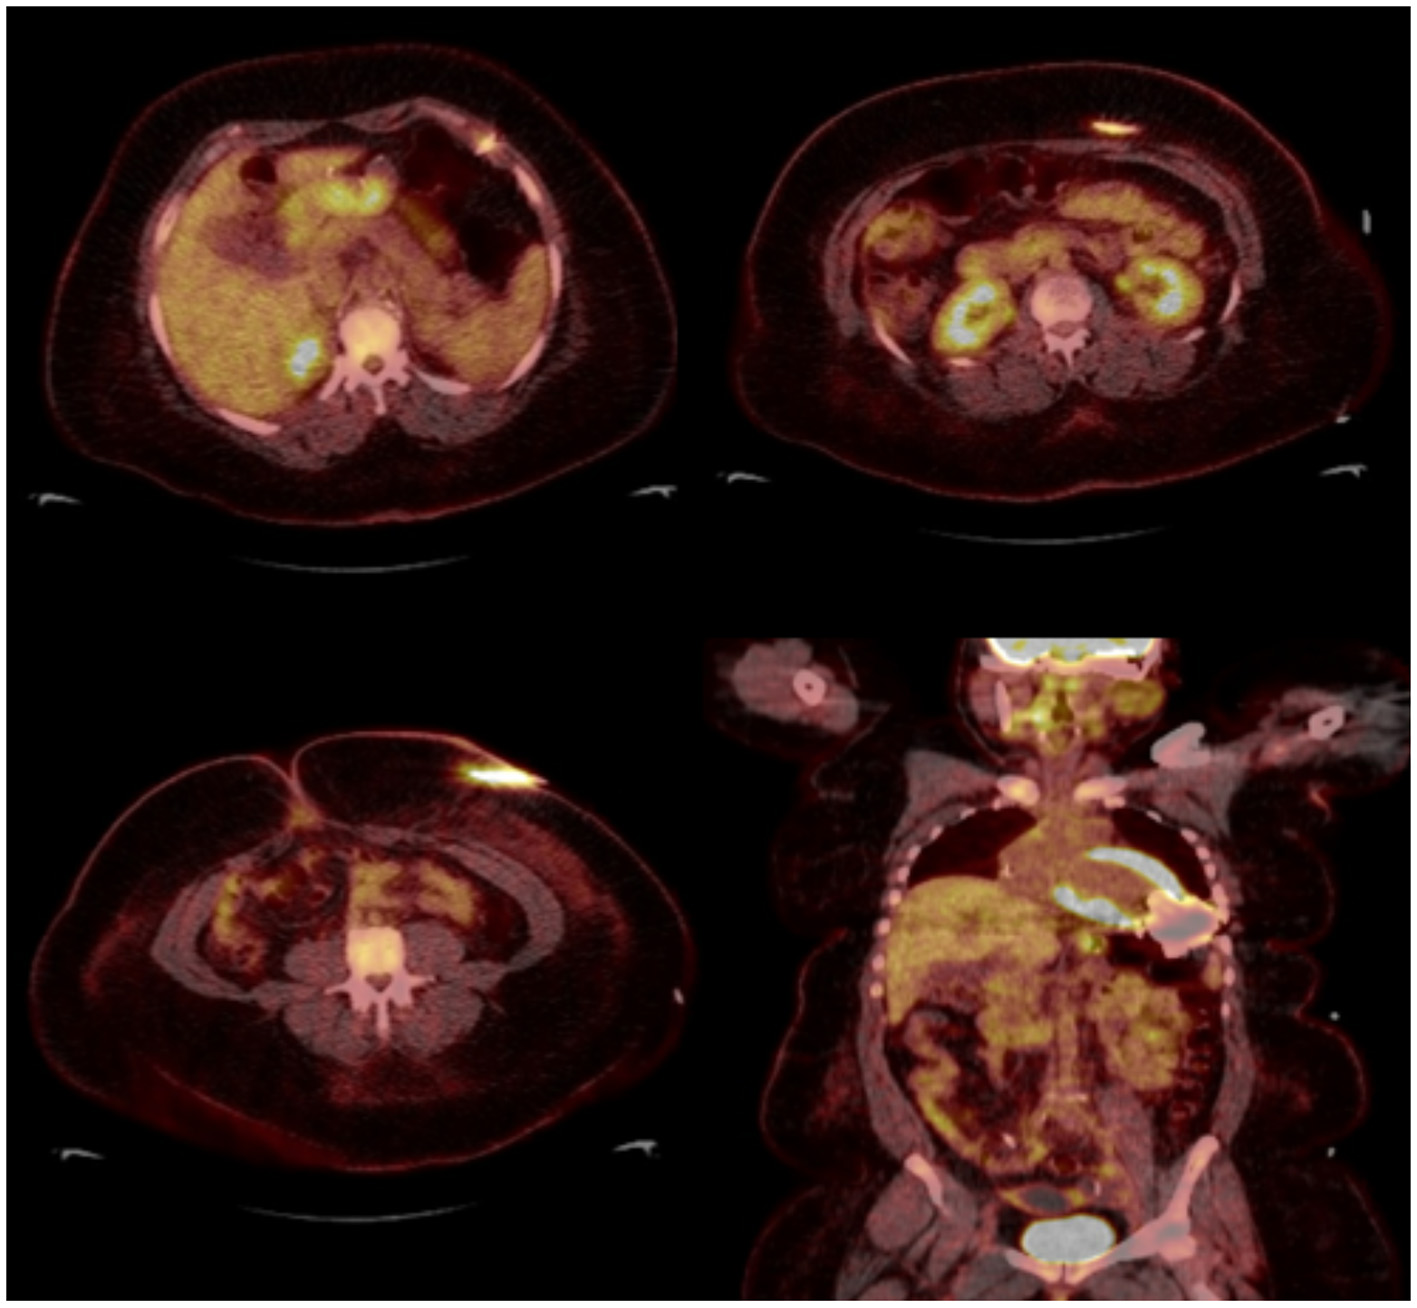

LVAD DLI is the most common LVAD-specific infection because the driveline exit creates an entry tract for bacteria that can attach to prosthetic material with bacterial biofilm. DLI is sub-divided into deep and superficial. Both types involve soft tissue surrounding the driveline exit, whereas deep infections also involve the fascia and muscle layers (27). No imaging modality can definitely exclude deep tissue infection, thus imaging in diagnosis of LVAD infections remains a challenge and is based mostly on observational data (28). Soft tissue ultrasound can help identify fluid collections around the driveline but cannot rule out deeper infections. TTE and TEE are often not useful in this setting unless concomitant endocarditis is suspected. CT is commonly used given the ability to detect deeper DLI demonstrated by the presence of abscess and fat stranding but can be limited by metal device artifact. The sensitivity and specificity of CT has not yet been established.

18F-FDG PET-CT and tagged WBC scan have emerged as more accurate modalities for detection of LVAD infection based on mostly small non-randomized studies (29–31). Correlating the anatomic findings, for example an abscess with the metabolic information is particularly useful. A major limitation of 18F-FDG PET-CT is the presence of non-specific uptake that can be present not only in early post-cardiac surgery but even years after LVAD implantation described as a post-operative inflammatory response. This tends to be characterized by a lesser degree of uptake and the reading clinician should become familiar with this presentation. Another consideration is the normal uptake pattern in patients with prosthetic materials due to foreign-body chronic low-grade inflammation. This is frequently seen when Dacron material is present in the LVAD outflow. Vaugelade et al. considered that a circumferential and homogeneous 18F-FDG uptake was a negative pattern for infection, defining positivity as a focal 18F-FDG uptake observed on both attenuation-corrected and uncorrected images in order to avoid overcorrection artifacts (31) (Figures 5, 6).

Figure 5

Thirty eight year-old female with end-stage heart failure s/p LVAD (Heart Mate 3) presented with drainage around driveline exit site and abdominal pain. She was treated with oral antibiotics for several weeks but continued to have symptoms. 18F-FDG PET-CT was obtained to assess extent of infection and showed increase FDG uptake surrounding LVAD driveline in the anterior abdominal wall without collections. She underwent driveline debridement for DLI and the driveline exit was relocated medially.

Figure 6

Forty seven year-old male with ischemic cardiomyopathy s/p LVAD (Heart Mate 3) presented with suspected DLI, with wound cultures positive for Candida Albicans. 18F-FDG PET-CT showed FDG activity in the pericardium, mediastinum, surrounding LVAD pump, driveline and sternum consistent with deep and superficial LVAD infection. He was managed with systemic lifelong antifungal therapy.